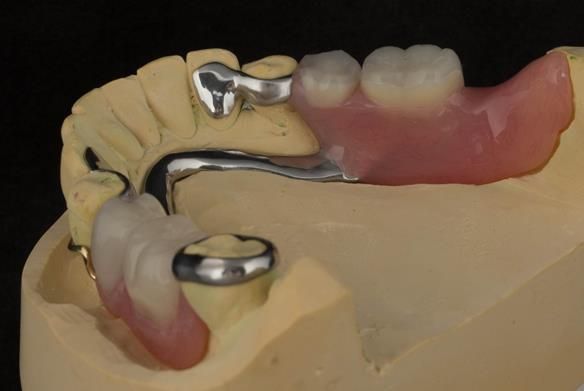

This newsletter describes in step by step detail Angela's transition through immediate partial dentures to crown supported definitive metal based dentures.

The clinical situation and treatment process is shown in detail below with photographs. I (Finlay Sutton) provided the clinical work and Rowan Garstang provided the technical work.